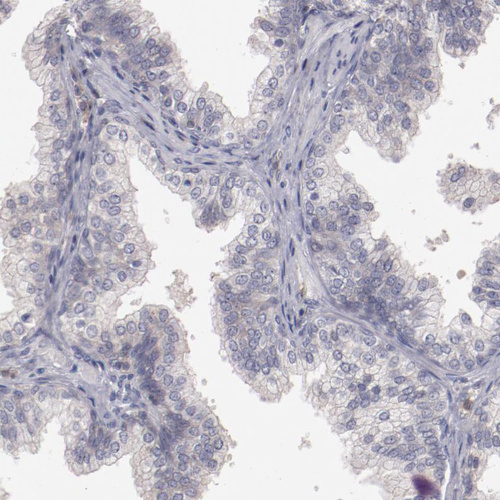

Immunohistochemistry analysis in human liver and prostate tissues using HPA002027 antibody. Corresponding MBL2 RNA-seq data are presented for the same tissues.